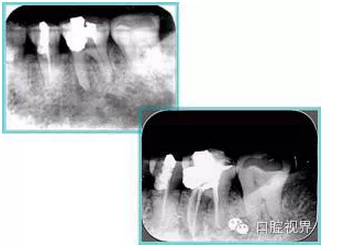

左圖和上圖為干髓治療后牙齒,齲齒疏通后進行根管充填。